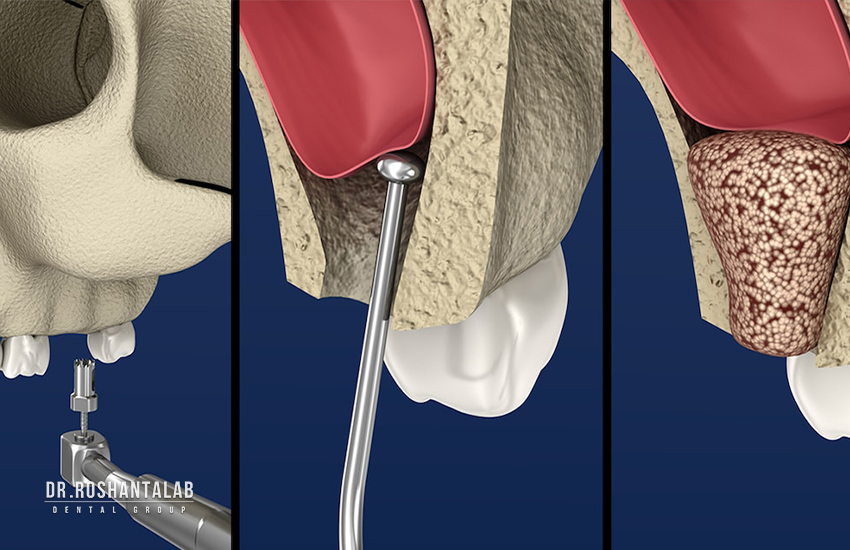

۲. جراحی سینوس لیفت (Sinus Lift)

در فک بالا، در ناحیه دندانهای آسیاب (خلفی)، حفرههای هوایی بزرگی به نام سینوسهای ماگزیلاری وجود دارند. وقتی دندانهای آسیاب بالا کشیده میشوند، استخوان زیر سینوس به سرعت تحلیل رفته و کف سینوس به سمت پایین (سمت دهان) افتادگی پیدا میکند. در نتیجه، استخوان کافی برای ایمپلنت باقی نمیماند و اگر جراح ایمپلنت را بکارد، نوک ایمپلنت وارد فضای سینوس شده و باعث عفونت سینوزیت میشود. در این شرایط، جراحی “سینوس لیفت” (بالا بردن کف سینوس) انجام میشود. غشای سینوس با احتیاط به بالا رانده شده و زیر آن پودر استخوان ریخته میشود. سینوس لیفت باز (Open Sinus Lift) معمولاً نیازمند ۶ ماه زمان بهبودی پیش از کاشت یا قرار دادن روکش است.